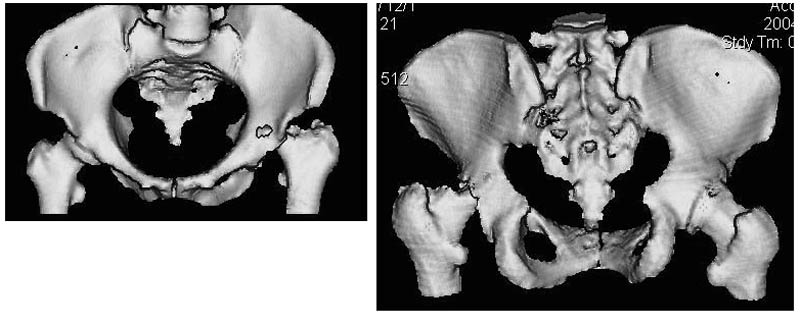

Женщина, 45 лет. В марте перенесла левосторонний коксит неизвестной этиологии. Специфику и онкологию исключили.

Интраартикулярных инъекций не было. Сейчас процесс клинически и рентгенологически - стабилизировался. Состояние вполне удовлетворительное.Предполагается тотальное эндопротезирование с пластикой полости аутокостью. Возможна ли бесцементная <чашка>? Заранее благодарю! С уважением,А.В.Владзимирский

Дополнение - проконсультировался с женой-она специалист рентгенолог - на КТ большое колиество мягкотканного компонента - ищите микоплазмы или бруцеллу. Я склоняюсь к виопсии.

Уважаемый коллега! Последняя версия - мы пролистали ренгенологическую книженцию-так картинка вполне подходит под сустав Шарко (neuropatic joint ). В тазобедренном суставе патология редкая (но меткая). Ищите причину - варианты - нейросифилис, сирингомиелия, опухи спинного мозга (и выше тоже) компрессия спинного

мозга извне, рассеяный склероз, алкоголизм. А так-же : склеродерма ,Рейно,ревматоидный артрит, амилоидная инфильтрация нервов,и это не считая всяких менингеомиелоцеле,asymbolia,Riley-Day syndrom,и все возможные другие нейропатии. На данном этапе не спешите оперировать(протезирование протиопоказано при нейропатических суставах),проконсультируйтесь с классным невропатологом,сделайте МЯР головного озга и

весь позвоночник. И держите нас в курсе - случай крайне интересный :)